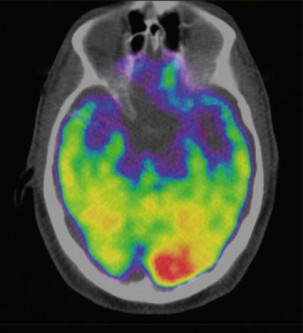

A scan of a brain used in a study carried out by Massachusetts General Hospital and Harvard Medical School which associates the brain region called the amygdala, an area linked to stress, to greater risk of heart disease and stroke is seen in an undated image released January 11, 2017 by The Lancet which published the reasearch. PHOTO: REUTERS